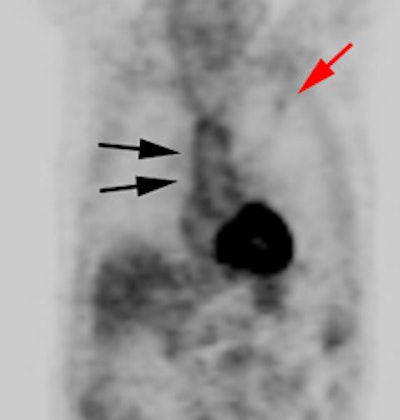

Vascular graft activity: The patient below had a prior graft repair of an ascending aortic aneurysm. Tracer uptake can be seen in the ascending aortic graft (black arrows). The patient also has a left upper lobe lung cancer (red arrows). |

|